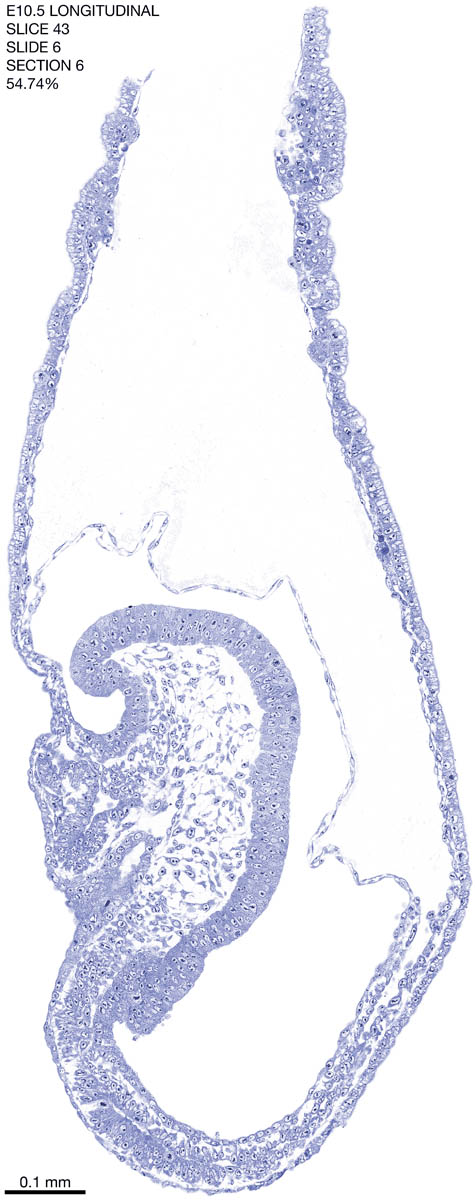

E10.5 Longitudianal Archive This page contains jpg files of ALL SLICES (each 3µm thick) that were scanned of the E10.5 longitudinally cut specimen. Download: Large | High Res Download: Large | High Res Download: Large | High Res Download: Large | High Res Download: Large | High Res Download: Large | High Res Download: Large | High Res Download: Large | High Res Download: Large | High Res Download: Large | High Res Download: Large | High Res Download: Large | High Res Download: Large | High Res Download: Large | High Res Download: Large | High Res Download: Large | High Res Download: Large | High Res Download: Large | High Res Download: Large | High Res Download: Large | High Res Download: Large | High Res Download: Large | High Res Download: Large | High Res Download: Large | High Res Download: Large | High Res Download: Large | High Res Download: Large | High Res Download: Large | High Res Download: Large | High Res Download: Large | High Res Download: Large | High Res Download: Large | High Res Download: Large | High Res Download: Large | High Res Download: Large | High Res Download: Large | High Res Download: Large | High Res Download: Large | High Res Download: Large | High Res Download: Large | High Res Download: Large | High Res Download: Large | High Res Download: Large | High Res Download: Large | High Res Download: Large | High Res Download: Large | High Res Download: Large | High Res Download: Large | High Res Download: Large | High Res Download: Large | High Res Download: Large | High Res Download: Large | High Res Download: Large | High Res Download: Large | High Res Download: Large | High Res Download: Large | High Res Download: Large | High Res Download: Large | High Res